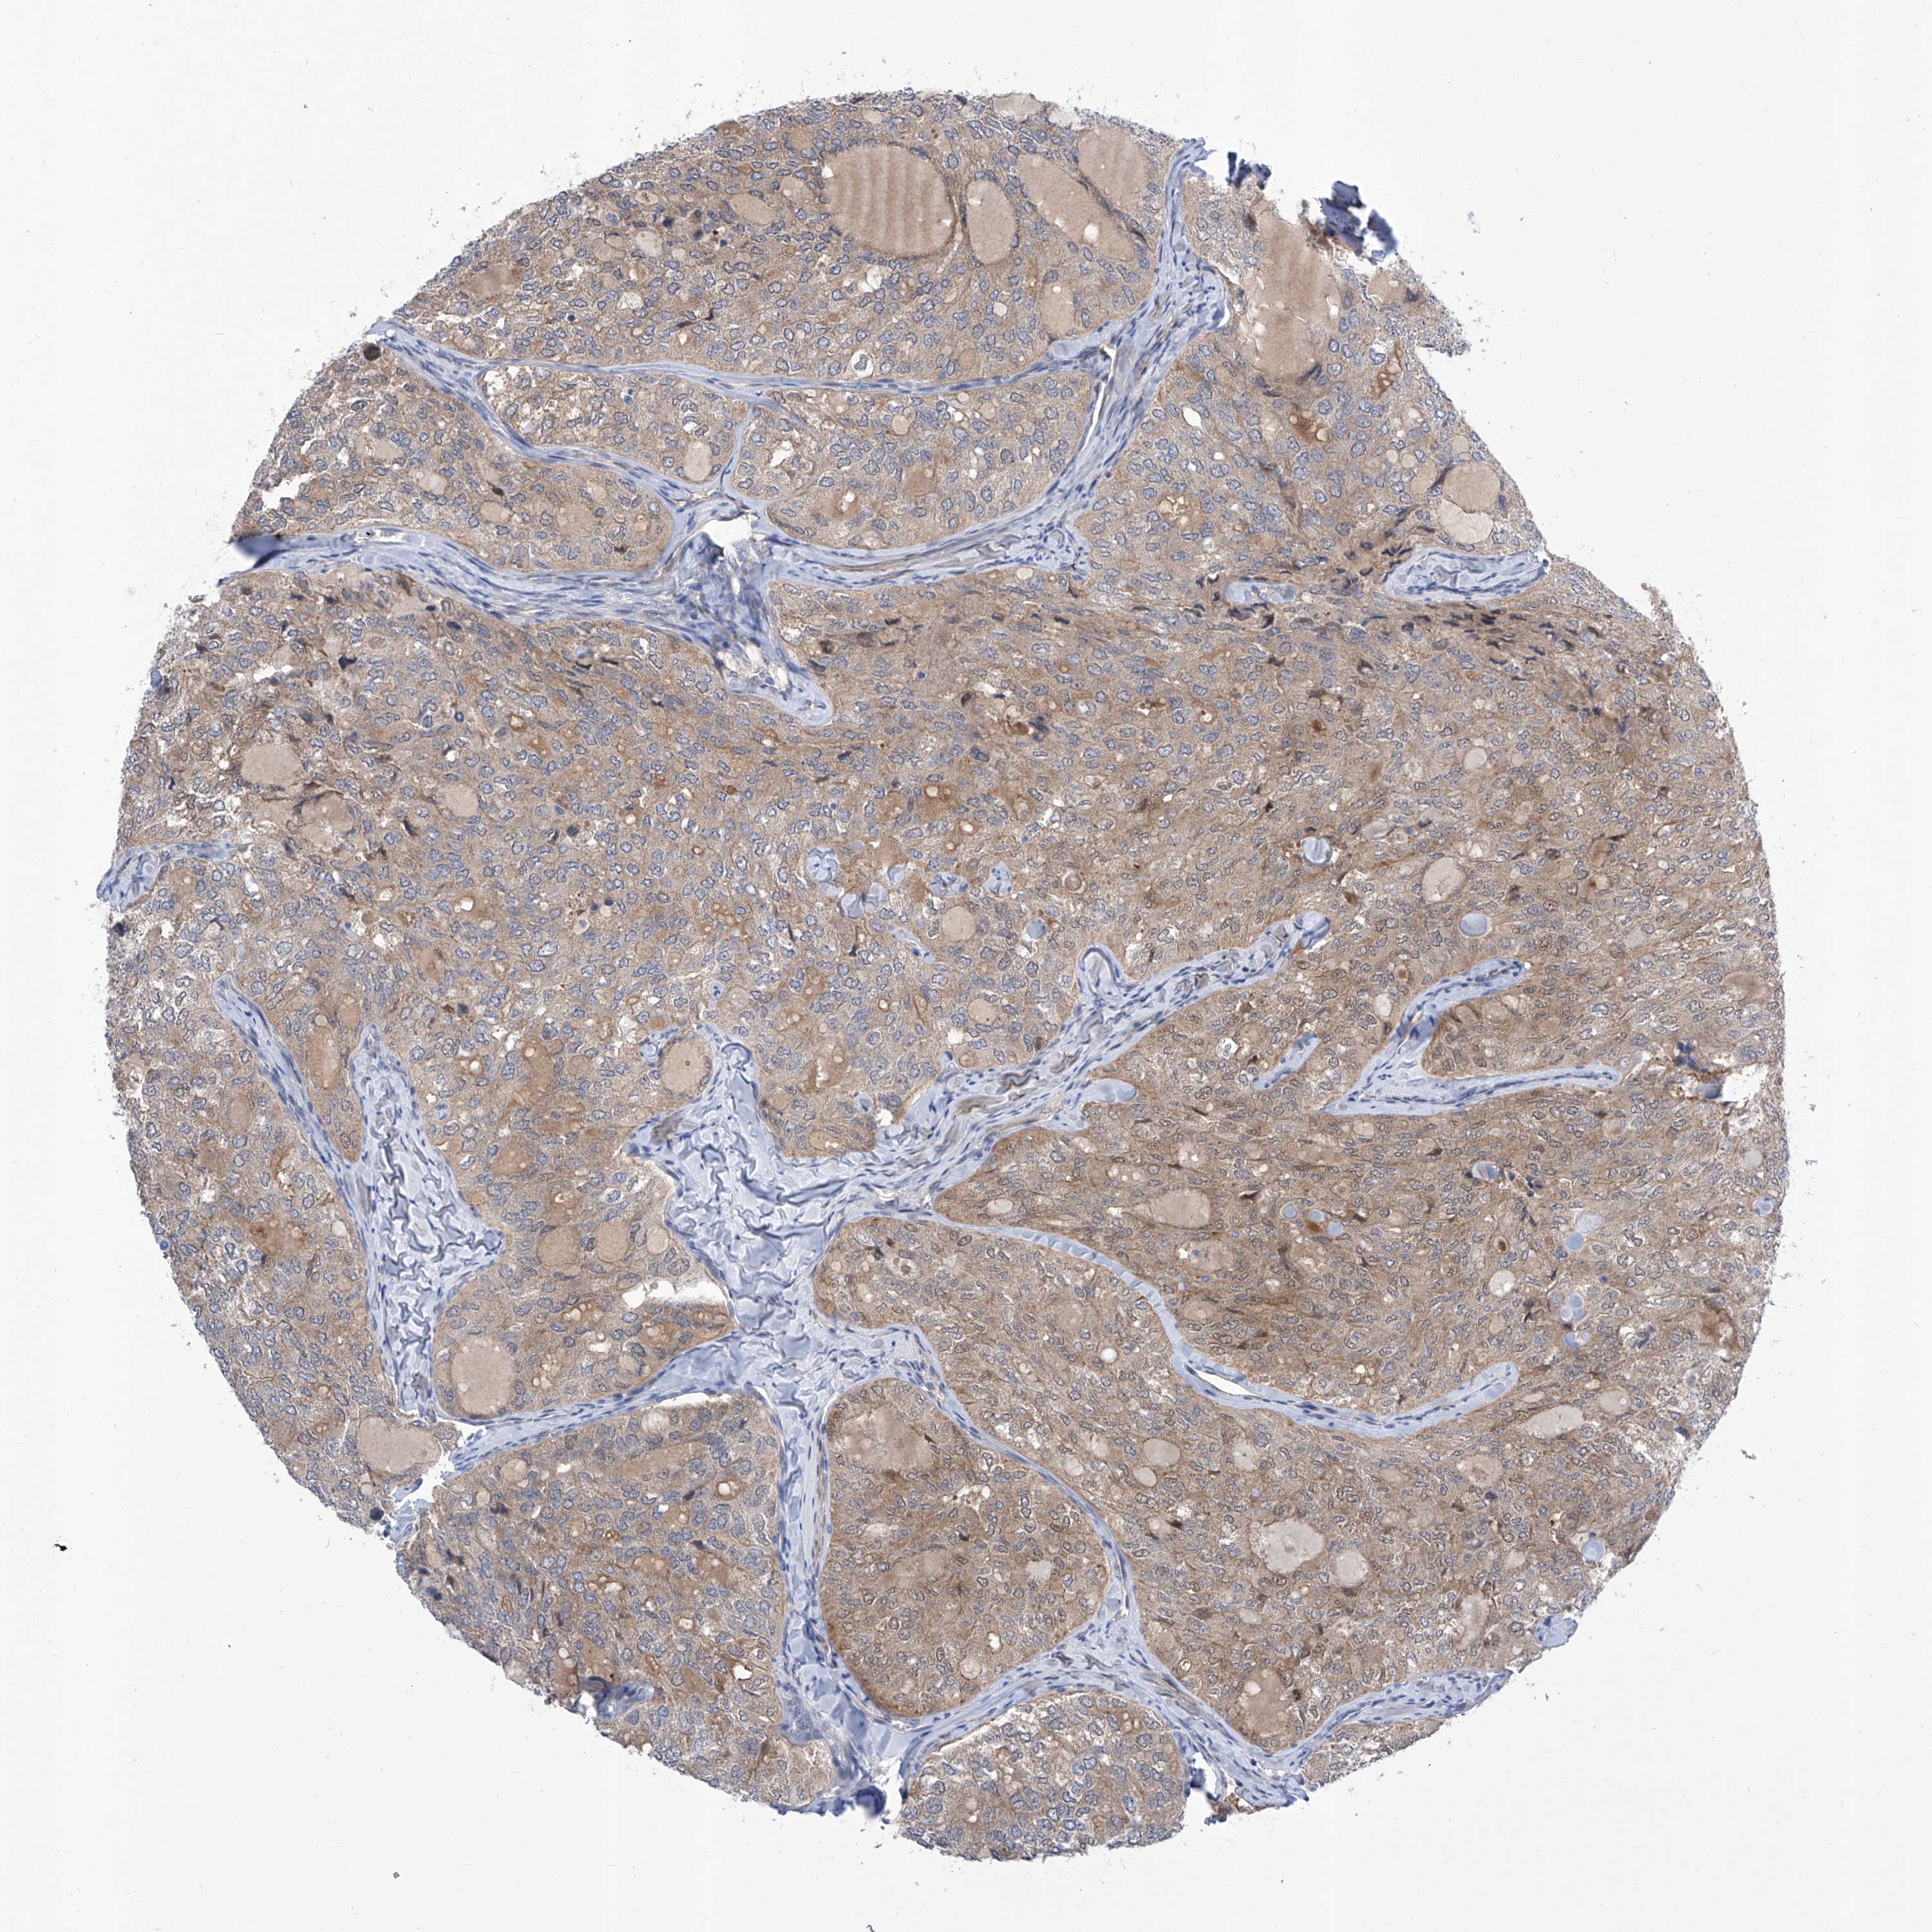

THYROID CANCER - Protein expressioni

A mouse-over function shows sample information and annotation data. Click on an image to view it in a full screen mode. Samples can be filtered based on level of antibody staining by selecting one or several of the following categories: high, medium, low and not detected. The assay and annotation is described here.

Note that samples used for immunohistochemistry by the Human Protein Atlas do not correspond to samples in the TCGA dataset.

Antibody stainingi

Antibody staining in the annotated cell types in the current human tissue is reported as not detected, low, medium, or high, based on conventional immunohistochemistry profiling in selected tissues. This score is based on the combination of the staining intensity and fraction of stained cells.

Each image is clickable and will lead to virtual microscopy that enables deeper exploration of all samples and also displays staining intensity scores, fraction scores and subcellular localization as well as patient and tissue information for each sample.

Antibody HPA030567

Antibody HPA030568

Staining

High

Medium

Low

Not detected

Intensity

Strong

Moderate

Weak

Negative

Quantity

>75%

75%-25%

<25%

None

Location

Nuclear

Cytoplasmic/membranous

Cytoplasmic/membranous,nuclear

Papillary adenocarcinoma, NOS

Follicular adenoma carcinoma, NOS